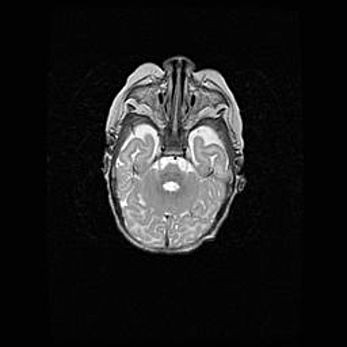

Наружная гидроцефалия с возможной атрофией височных областей.

Возраст: 28 дней

Вес: 3670 г

Пол: мужской

Окружность головы: 38 см

Срок гестации: 40 недель

Гидроцефалия головного мозга у новорожденных – это заболевание, которое характеризуется скоплением избыточного количества спинномозговой жидкости в желудочковой системе головного мозга в результате затруднения её перемещения от места выработки к месту поглощения в кровеносную систему или вследствие нарушения абсорбции. При открытой наружной форме гидроцефалии у новорожденных расширяются и переполняются субарахноидные пространства.

При нормотензивных  формах,  которые,  как  правило,  являются  следствием  перенесенных ишемических  повреждений  паренхимы  мозга,  возможно  сочетание микроцефалии  с нормотензивной гидроцефалией. В основе данных изменений лежит атрофия больших полушарий с преимущественной  локализацией  в  лобно-височных  областях.